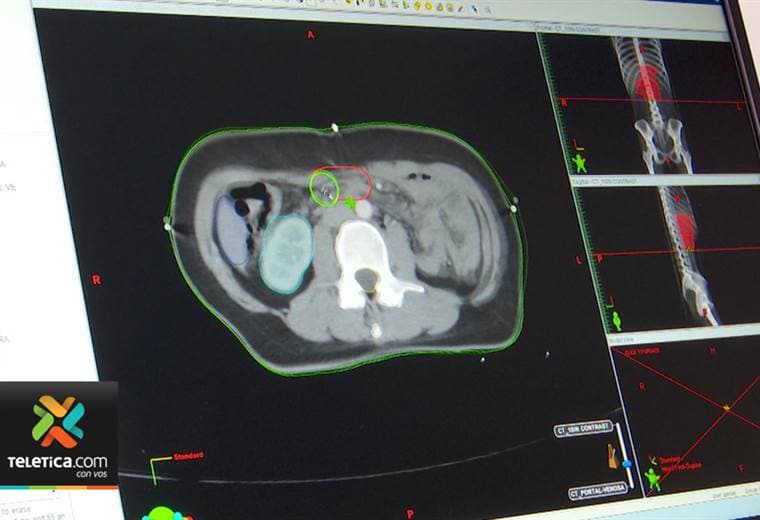

Shaun Tierney vive con un agresivo cáncer de riñón desde hace 12 años, una duración inimaginable en el momento del diagnóstico, pero posible gracias a la investigación reconocida este año por el Premio Nobel de Medicina.

Los hijos de este ingeniero de 64 años acababan de dejar la casa familiar cuando "el suelo se derrumbó bajo sus pies", cuenta a la AFP Tierney, quien tiene un cáncer raro conocido como carcinoma de células renales.

En 2007, cuando Tierney supo que tenía cáncer, le dijeron que tenía una probabilidad de 3% a 5% de vivir cinco años.

Que no se cumplieran los malos pronósticos se debe a un tratamiento llamado Sutent (sunitinib), derivado directamente del trabajo de los investigadores, y que representa un nuevo tipo de medicamento diseñado para detener el crecimiento de los vasos sanguíneos que alimentan las células de los tumores.